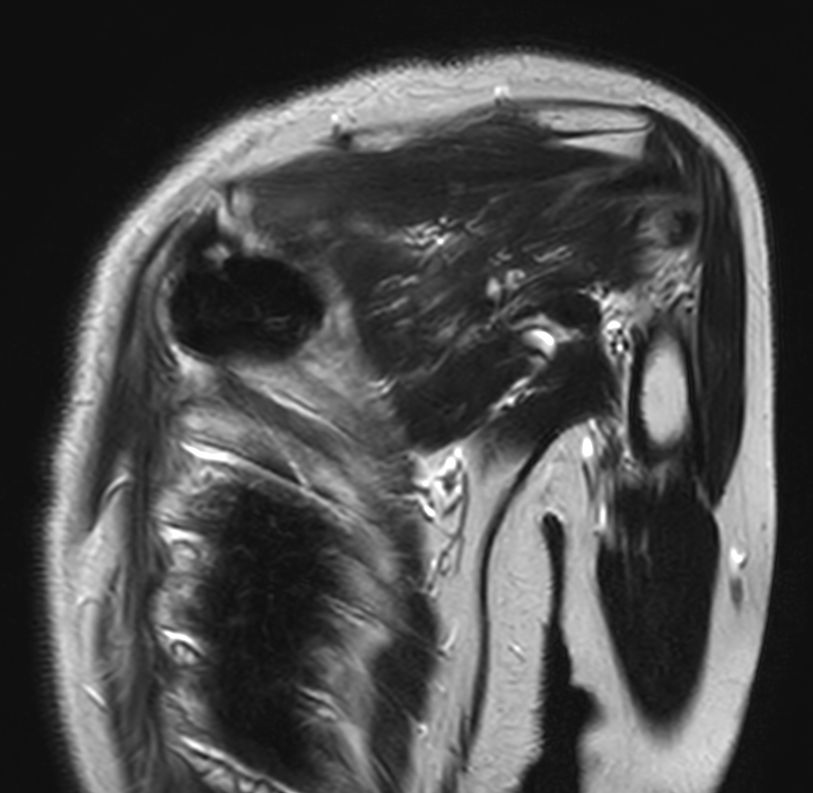

Patient with a thorax soft tissue lesion. ExamCard includes Compressed SENSE to shorten the scan time, MultiVane XD to acquire motion-free diagnostic images, 3D VANE XD helping to reduce motion artifacts during free breathing and 4D FreeBreathing to perform multi-phase contrast-enhanced MRI studies.

T2w TSE MultiVane XD - Free Breathing